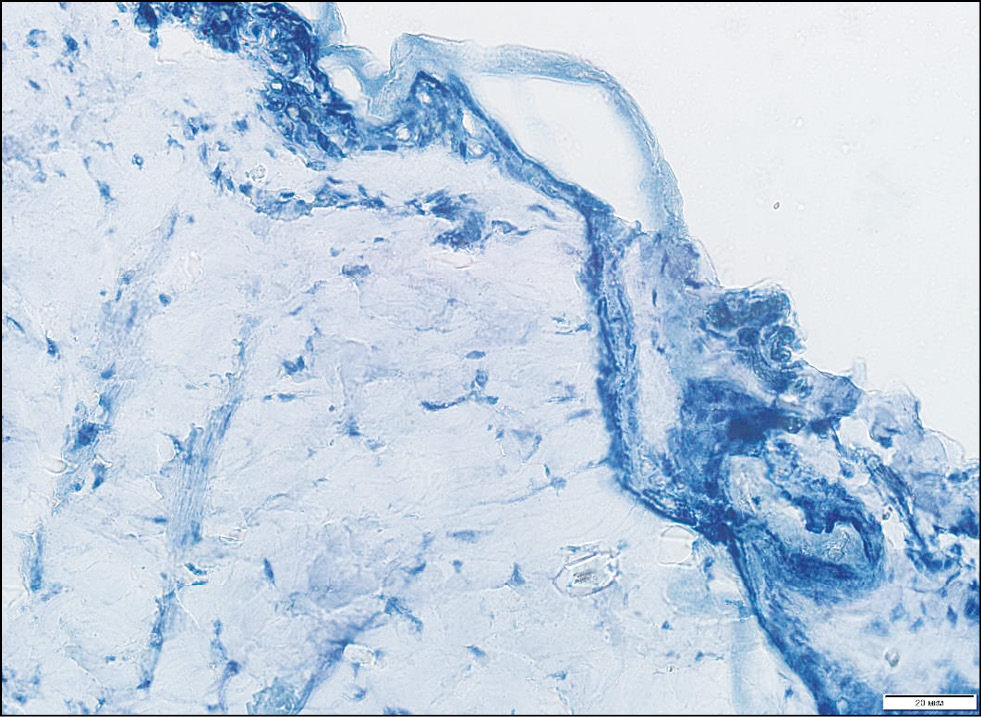

Рис. 3. Контрольный образец (кожа спины крысы до нанесения топического средства с 0,4% Сферометаллохлорином™). Окраска Суданом III, х200.

Fig. 3. Control sample (rat back skin before application of topical agent with 0.4% Spherometallochlorin™). Painting by Sudan III, x200.

Рис. 4. Гистологическая картина кожи спины крысы через 15 мин после нанесения топического средства с 0,4% Сферометаллохлорином™. Окраска Суданом III, х200.

Fig. 4. Histological picture of the skin of the back 15 minutes after application of a topical agent with 0.4% Spherometallochlorin™. Painting by Sudan III, x200.

Подэтап 1Б. При исследовании гистологической картины до нанесения геля (рис. 3) со Сферометаллохлорином™ эпидермис и дерма интактны. Через 15 мин экспозиции (рис. 4) заметно скопление суданположительного материала в придатках кожи; кроме того, наблюдается его распространение рядом с волосяными фолликулами в интерстиций дермы. Через 30 мин экспозиции (рис. 5) отмечается распространение суданположительного материала в интерстиции в виде мелких капель по ходу коллагеновых волокон на глубину до подкожно-жировой клетчатки. Через 45 мин экспозиции в препарате визуализируются крупные сформированные липидные капли в дерме и более интенсивно прокрашенные липидные капли в подкожно-жировой клетчатке.

На основе полученных данных можно сделать вывод, что оптимальным временем экспозиции геля с фотосенсибилизатором является 30 мин, поскольку на этом этапе гель проникает в дерму по ходу коллагеновых волокон на глубину до подкожно-жировой клетчатки, что является обязательным условием для проведения процедуры ФДТ.